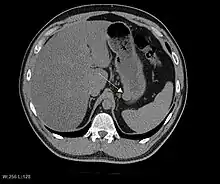

CT image of a GIST in the gastric cardia. The lesion appears submucosal, is hypervascular and protrudes intraluminally. Upper GI bleeding led to endoscopy, finding an ulcerated mass.

The purpose of radiologic imaging is to locate the lesion, evaluate for signs of invasion and detect metastasis. Features of GIST vary depending on tumor size and organ of origin. The diameter can range from a few millimeters to more than 30 cm. Larger tumors usually cause symptoms in contrast to those found incidentally which tend to be smaller and have better prognosis.[4][13] Large tumors tend to exhibit malignant behavior but small GISTs may also demonstrate clinically aggressive behavior.[14]